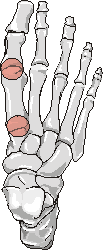

- Rheumatoid Arthritis: Erosions  and subluxation 1st MTP joint

+++